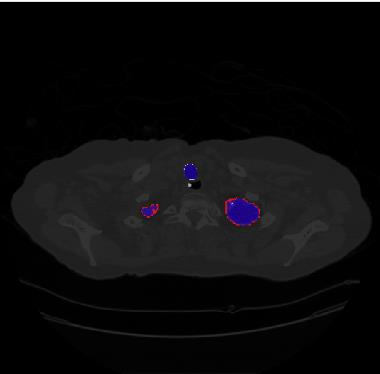

Segmentation of lung tissue in computed tomography (CT) images is a precursor to most pulmonary image analysis applications. Semantic segmentation methods using deep learning have exhibited top-tier performance in recent years. This paper presents a fully automatic method for identifying the lungs in three-dimensional (3D) pulmonary CT images, which we call it Lung-Net. We conjectured that a significant deeper network with inceptionV3 units can achieve a better feature representation of lung CT images without increasing the model complexity in terms of the number of trainable parameters. The method has three main advantages. First, a U-Net architecture with InceptionV3 blocks is developed to resolve the problem of performance degradation and parameter overload. Then, using information from consecutive slices, a new data structure is created to increase generalization potential, allowing more discriminating features to be extracted by making data representation as efficient as possible. Finally, the robustness of the proposed segmentation framework was quantitatively assessed using one public database to train and test the model (LUNA16) and two public databases (ISBI VESSEL12 challenge and CRPF dataset) only for testing the model; each database consists of 700, 23, and 40 CT images, respectively, that were acquired with a different scanner and protocol. Based on the experimental results, the proposed method achieved competitive results over the existing techniques with Dice coefficient of 99.7, 99.1, and 98.8 for LUNA16, VESSEL12, and CRPF datasets, respectively. For segmenting lung tissue in CT images, the proposed model is efficient in terms of time and parameters and outperforms other state-of-the-art methods. Additionally, this model is publicly accessible via a graphical user interface.